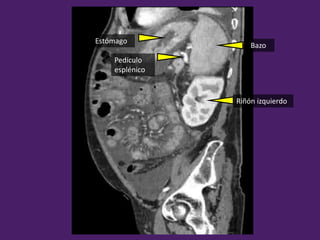

Bazo

Estómago

Pedículo

esplénico

Riñón izquierdo

Riñón

izquierdo